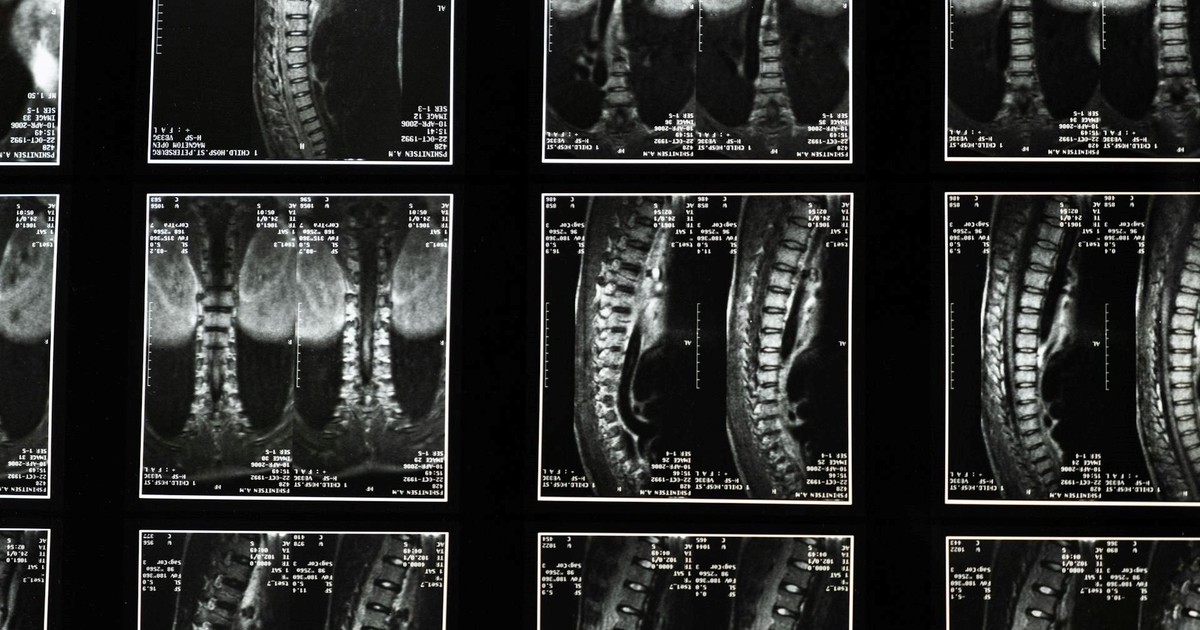

El especialista definió a la artrosis de cadera como “una bisagra sin aceite, duele, cruje y te frena”